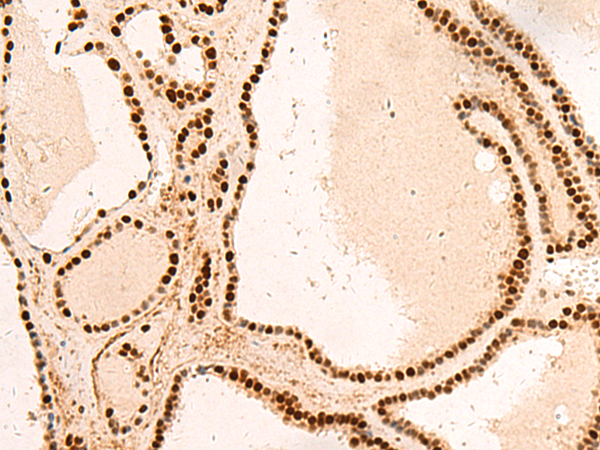

分类: 科研抗体货号: P10040别名:应用: IHC反应种属: Human, Mouse